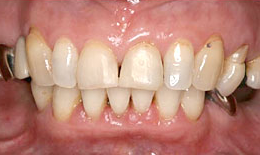

インプラント症例(9)女性 58歳

治療方法

- インプラントを6本埋め込んで、セラミックスクラウンを被せた